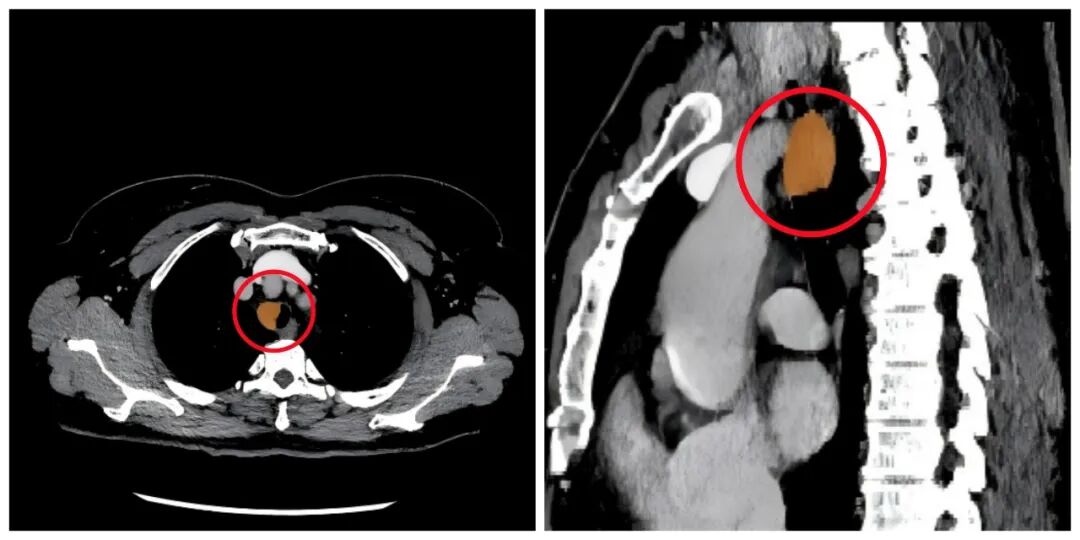

患者术前CT影像,圈内示肿物

肿瘤位于胸段气管,造成气管明显狭窄